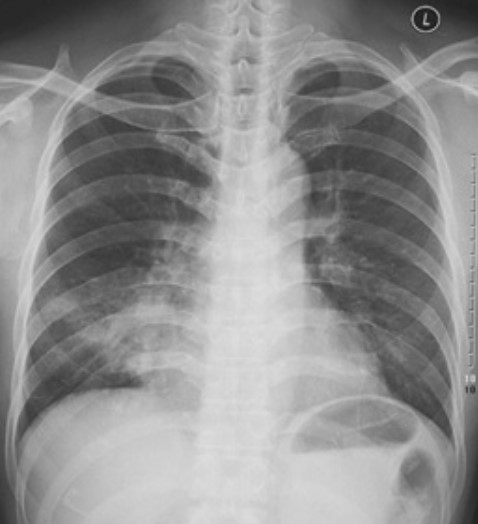

4.根據(jù)下圖請(qǐng)做出正確診斷

A.右側(cè)肺炎

B.兩下肺炎

C.右下肺肺癌

D.正常胸片

答案提示:【該題針對(duì)“ X線-肺炎 ”知識(shí)點(diǎn)進(jìn)行考核】